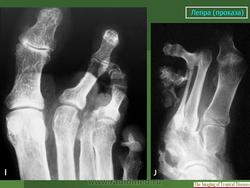

Здесь также часто наступают нарушения целости костей -- истинные патологические переломы, без периостальной активности, без заживления костной мозолью. Переломы ускоряют рассасывание костей. Их не следует смешивать рентгенологически с костными дефектами на протяжении метафиза или диафиза кости. Иногда исчезновение костной ткани происходит сильнее проксимально, чем дистально, и отдельные костные участки могут "повиснуть" в мягких тканях. Отсюда они отходят, отторгаются наружу наподобие секвестров при костном панариции; трудно сказать, в какой мере здесь играет роль совсем необязательная вторичная инфекция, крайне вялая, если она действительно имеет место. Иногда развиваются истинные неврогенные остеоартропатии - лепрозные остеоартро-патии.

Вместе с тем при нервной лепре наблюдаются также настоящие костные анкилозы. Чаще всего это происходит в области плюсне-пред-плюсневых суставов, а между суставами малых трубчатых костей кистей и стоп анкилозы при проказе не развиваются. Калечения усугубляются еще тягой мышц. Происходит уклонение фаланг в стороны, большие расхождения суставных концов, крайние деформации. Мы наблюдали и лоозеровекие зоны перестройки костей на обычных и особенно необычных местах, с нормальным или извращенным их течением и исходом.